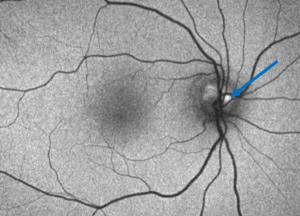

![]() Figure 3. Fundus autofluorescence of the right eye showing hyper-autofluorescence of the optic disc, more so superior-temporally, indicating optic disc drusen (blue arrow). |

![]() Figure 4. Fundus autofluorescence of the left eye showing hyper-autofluorescence of the optic disc indicating optic disc drusen (blue arrow). A mixed patch of hypo- and hyper-autofluorescence (hypo-autofluorescence surrounded by hyper-autofluorescence, yellow arrow) surrounded by hypo-autofluorescence (green arrow) is noted superior-temporal to the disc. This corresponds with the fibrovascular lesion with surrounding pigment disruption noted on fundus photos and is indicative of the inactive choroidal neovascular membrane. |